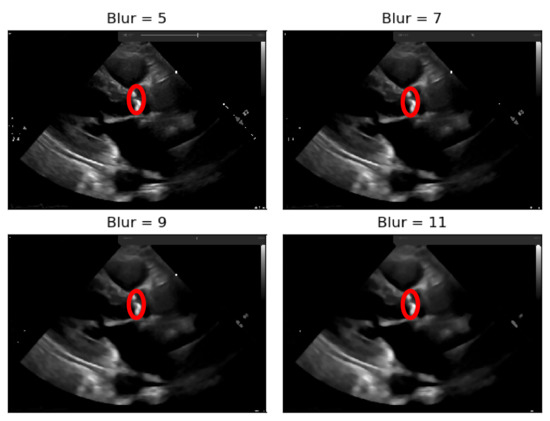

To the resulting images of this blurring phase, a binarization operation with a fixed pixel threshold value of 160 was produced, experimentally obtained by analyzing 48 cases of echocardiography images, where 255 corresponds to calcium, as seen in Figure 5. This initial approach of a using a fixed threshold is not sufficient for our problem at hand, since our images’ brightness may vary, given different data collection conditions. To tackle this issue, an adaptive binarization technique has to be performed, which will be further explained.

In Figure 5, it is noticeable that when the blurring parameter increases from 5 to 11, we get a cleaner image (without small white dots—noise). However, we can also notice that in the region of interest (marked with red circles), when the blur increases, we lose pixels, since the region gets smaller. To mitigate this, a mask dilation operator was applied to each region of interest.

Figure 5. Binarization of an echocardiography image, for each size of the kernel parameter applied—The red circle represents our ROI (aortic valve).